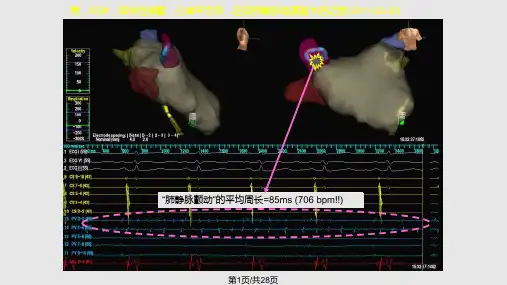

CARTO指导下环PV左房线性消融(米兰)

改良左房线性消融(LACA)隔离肺静脉

• 肺静脉节段性电隔离 VS. 左房线性消融 • 成功率:67% VS. 88%